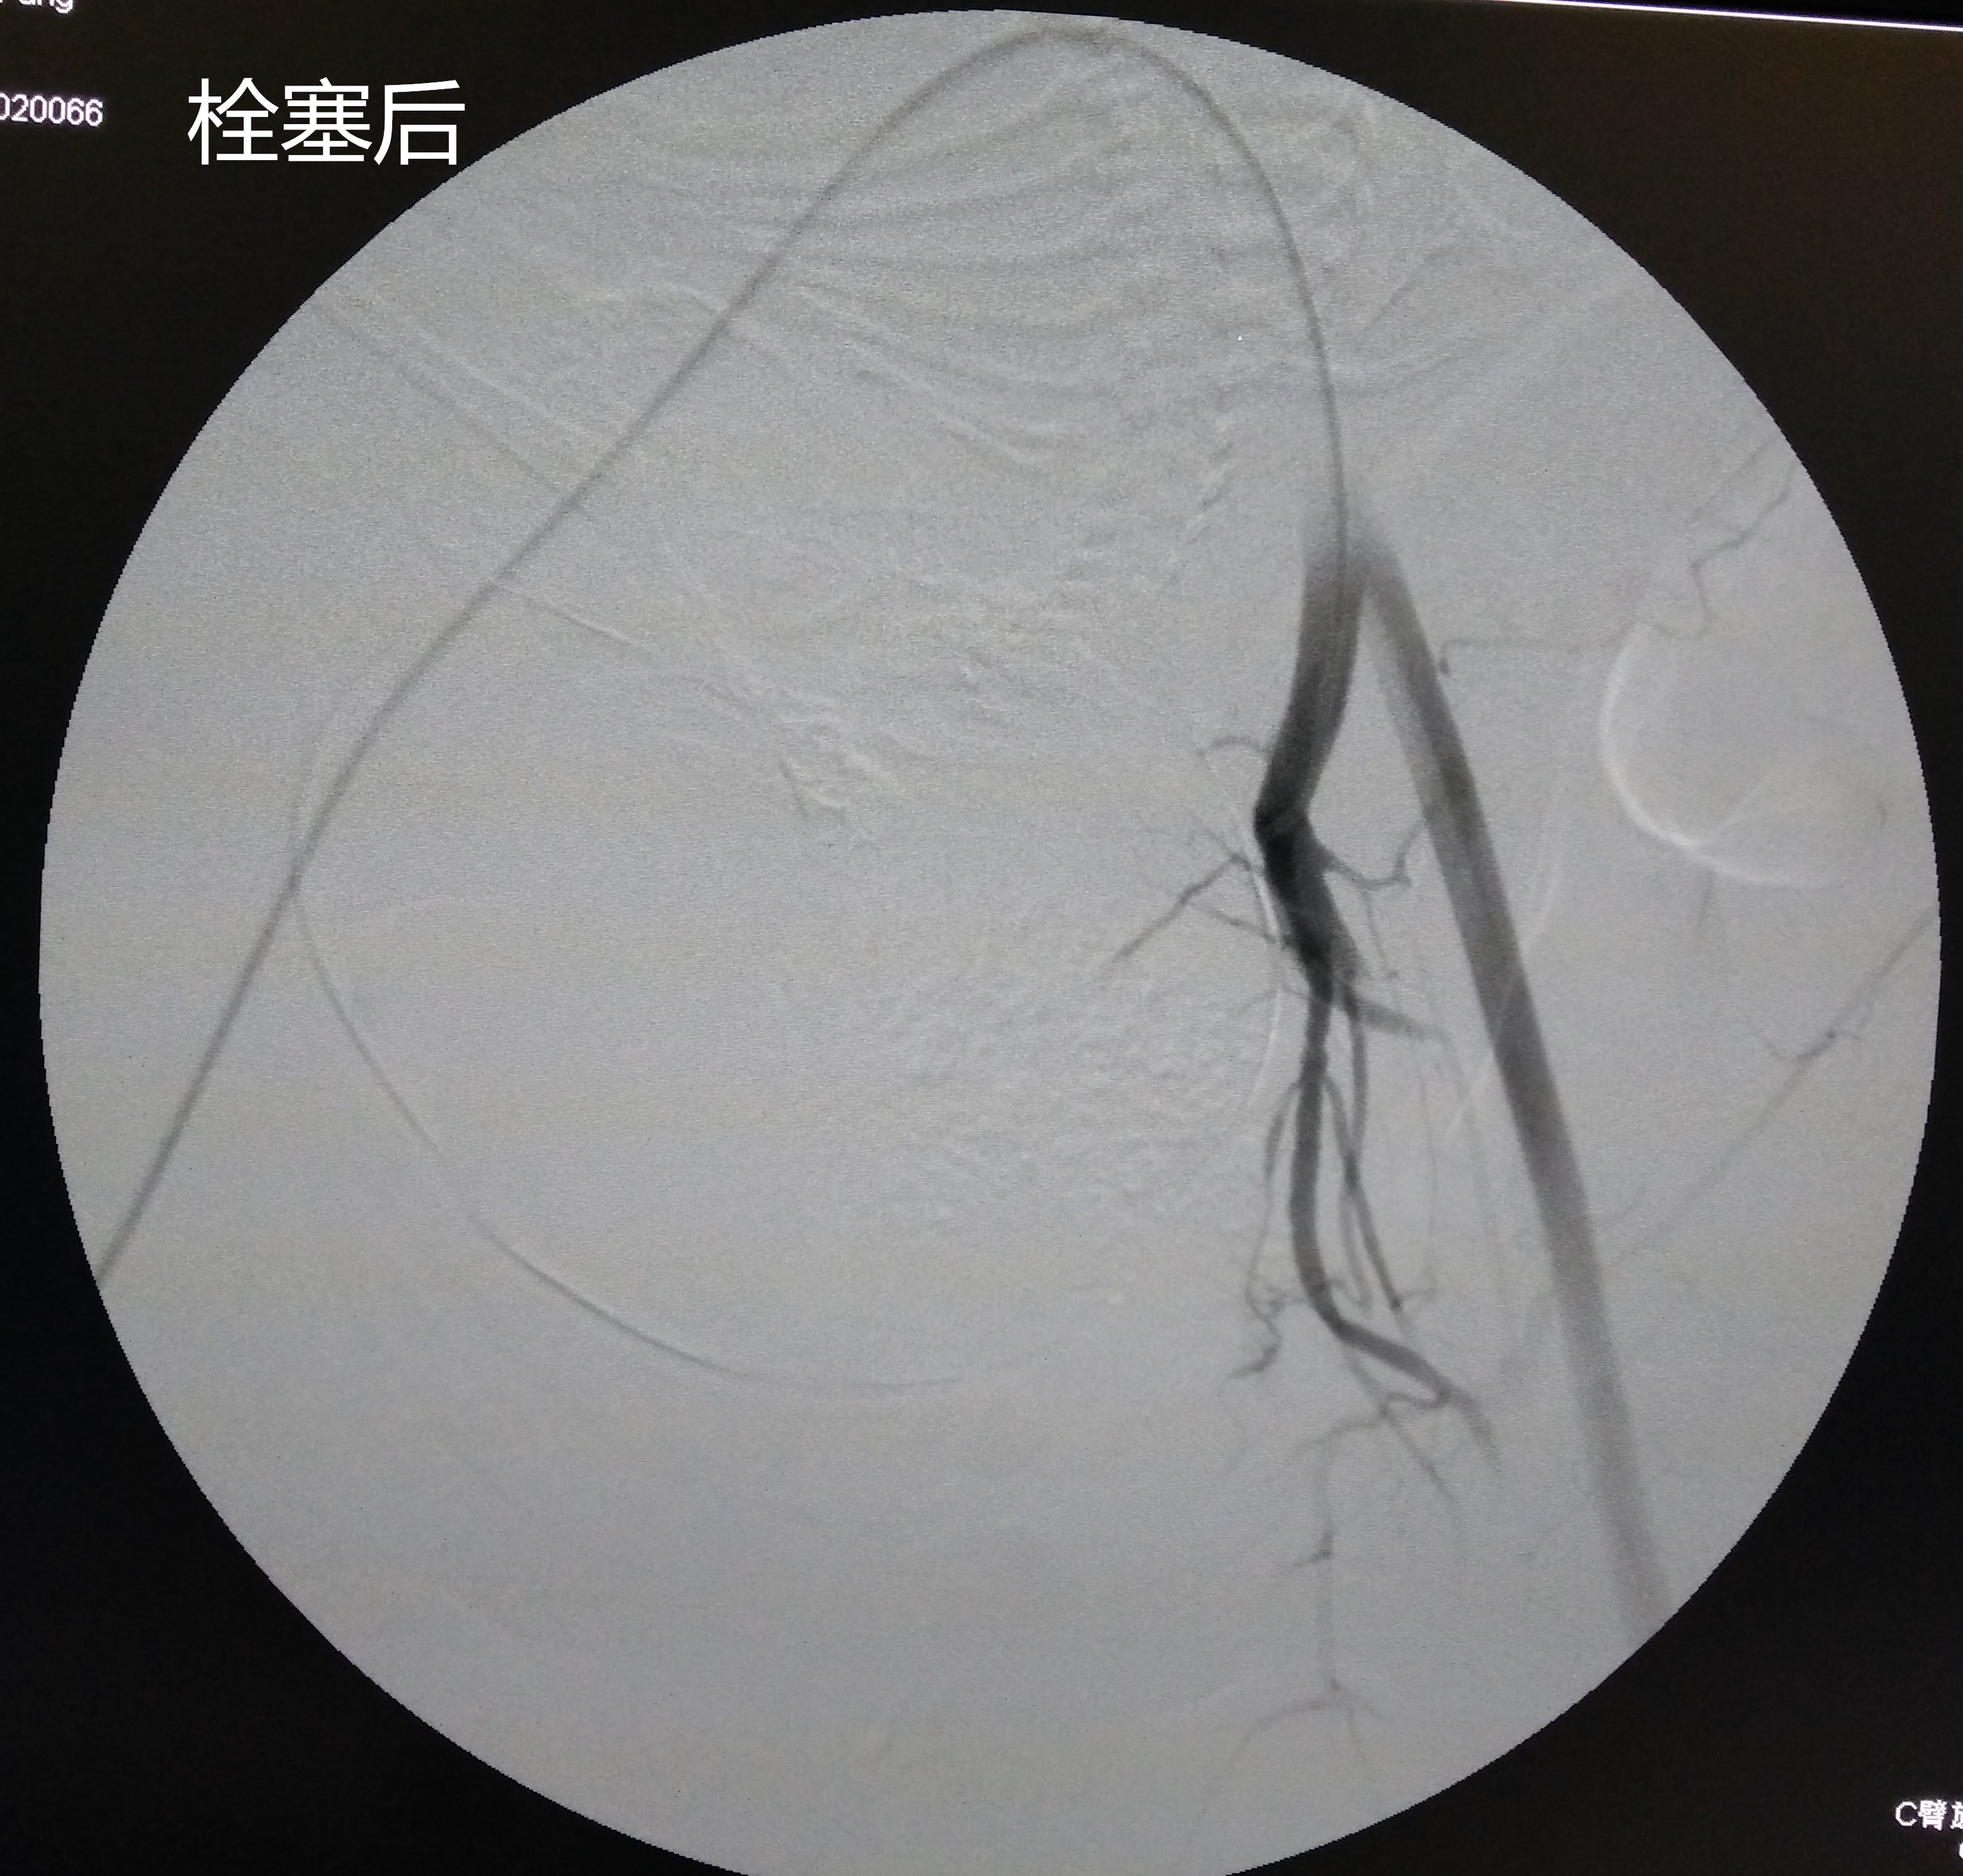

手术在数字减影血管造影机(DSA)引导下进行,手术由放射科唐小平主任、王琦、杨九炜医师操作,杜海云主管护师紧密配合。手术采用改良Seldinger技术穿刺右侧股动脉成功后,行左侧子宫动脉造影:左侧子宫动脉走行明显迂曲,管径明显增粗;遂将导管头端至于左侧子宫动脉中,经导管注入碘佛醇明胶海绵混悬剂经导管行子宫动脉栓塞术,栓塞完成后再次造影可见左侧子宫动脉主干以下不再显影。同法栓塞右侧子宫动脉成功后立即送入手术室行“子宫下段剖宫产术”。剖宫产术中出血约600ml,生命体征平稳,术后产妇安返产科病房,在产科医护人员的精心护理下,目前患者恢复良好,可下地活动。